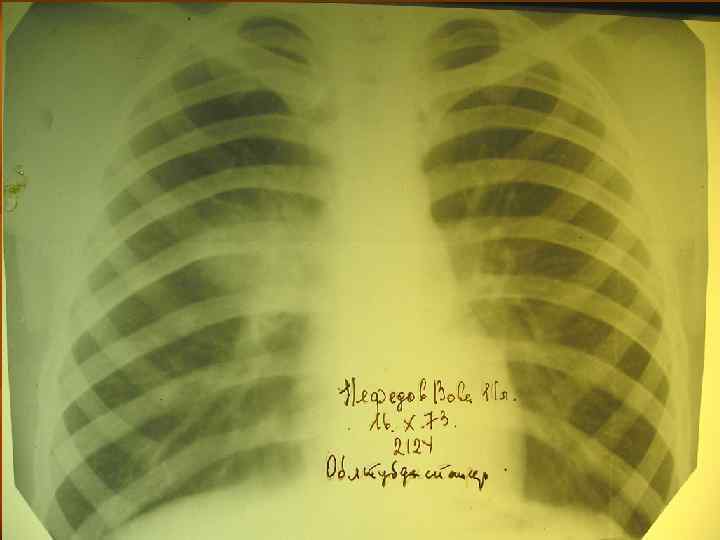

Туберкулез внутригрудных лимфатических узлов

Первичный туберкулезный комплекс (пневмоническая стадия) n Рентгенологическая картина: определяется инфильтрат «идущий» от периферии к корню легкого.

Первичный туберкулезный комплекс (стадия рассасывания) n Рентгенологическая картина: определяется фокусная тень связанная дорожкой с расширенным корнем (легочный аффект + лимфангоит +лимфоаденит).

Первичный туберкулезный комплекс (стадия организации и уплотнения) n Рентгенологическая картина: определяется плотная очаговая тень в легком и в корне не связанные между собой.

Первичный туберкулезный комплекс (стадия петрификации) n n Вариант клинического излечения Рентгенологически определяется петрификат в легком (очаг Гона) и в корне.

Первичный туберкулезный комплекс